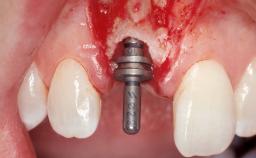

Late Flapless Placement of an Implant in a Maxillary Left Central Incisor Site

A 39-year-old male patient presented with a chief complaint of discomfort and gingival discoloration around his maxillary left central incisor. He was in good general health and was a non-smoker. His past dental history was significant because of the traumatic fracture of tooth 21 in a sporting accident at age 13. Initial dental treatment included endodontic therapy and a full-coverage restoration. The patient became symptomatic 5 years later, when structural failure of the tooth resulted in the dislodgment of the crown. Endodontic retreatment, apical surgery, and post-and-core restoration were performed.

Type of Implants One-Piece

Placement Protocol Early or late implant placement